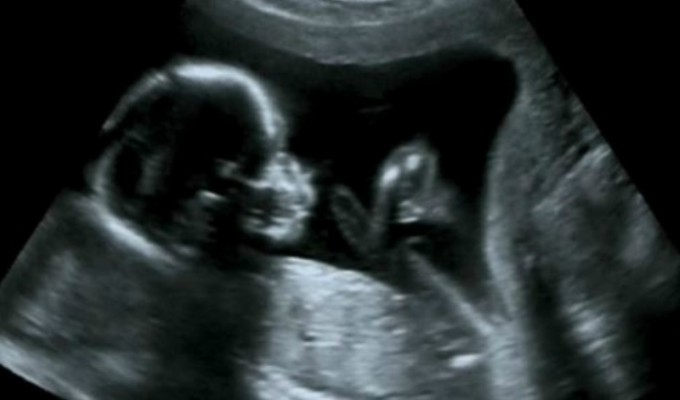

Un curioso y extraño caso sucedió en Colombia, donde una menor estuvo embarazada durante su propia gestación. Es decir que el feto tenía otro feto en su vientre, que correspondía al de un mellizo.

El caso médico se llama 'fetus in fetu', es un tipo de gemelo parásito muy poco desarrollado, una creación humanoide producida por accidente en cierto punto de la formación del cigoto previo a la formación del embrión. En la historia, se han reportado al menos unos 500 casos.

La recién nacida la luz del mundo a las 37 semanas y de inmediato fue sometida a una cirugía para sacar el feto en su interior. Este nació con saco amniótico, cordón umbilical, huesos y extremidades, pero sin corazón ni cerebro.